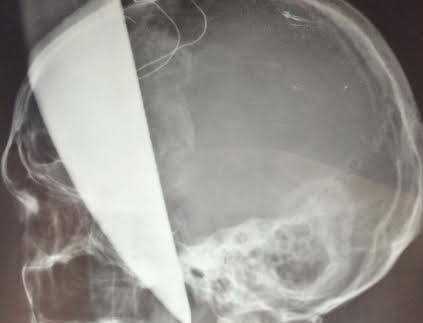

Bệnh viện Việt Đức phẫu thuật lấy dao bầu cắm xuyên não bệnh nhân

Do lưỡi dao nằm sát mạch máu lớn của não nên các bác sỹ phải dùng biện pháp mài vùng xương sọ quanh lưỡi dao để rút dao ra mà không làm đứt mạch máu não.